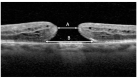

There is limited data on the presentation and surgical outcomes of idiopathic macular holes (IMH) for different ethnic and racial groups. Recognition of distinct, clinically-relevant patient subgroups may provide opportunities to identify specific unmet needs including possible barriers to optimal healthcare delivery. Medical records of patients who underwent surgery for IMH (between 2016 and 2022) at a large, urban retina practice were reviewed and self-reported ethnicity (Hispanic and non-Hispanic) and race (Asian, Black, White, and Other) were captured. The primary variables included (1) mean minimum linear diameter (MLD) at presentation and (2) surgical outcome (IMH closure status). Overall, mean MLD for all study eyes (515) was 366.1 μm, and surgical success was achieved in 489 (95.0%) eyes. Hispanic eyes presented with larger mean MLD (p = 0.002) compared to non-Hispanic eyes. Asian, Black, and Other eyes presented with larger mean MLD (p = 0.033, p < 0.001, p < 0.001) when compared to White eyes. The presentation of IMH varied in severity among different ethnic and racial groups. Hispanic patients were found to have worse preoperative visual acuity (VA), longer time to surgery, and larger mean MLD and BD compared to non-Hispanic participants. Black and Other patients were found to have worse VA, time to surgery, and larger mean MLD and BD when compared to White participants.

Figures